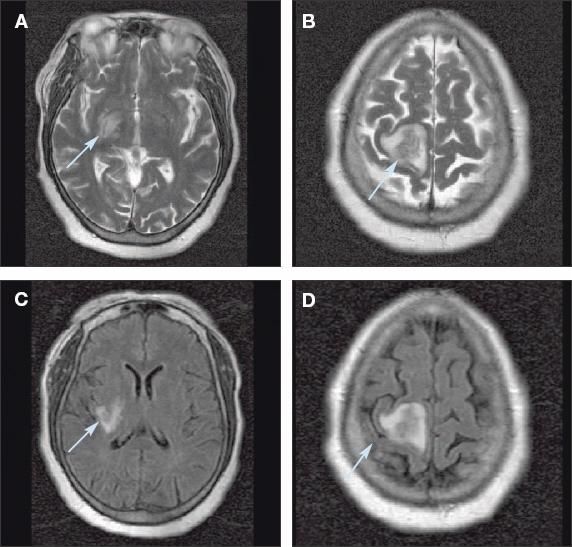

An MRI scan of the brain showed 2 discrete lesions in the right cerebral hemisphere, one in the right lateral basal ganglia and the other in the parasagittal right posterior frontal lobe centered within the precentral gyrus (Figure). There was no corresponding diffusion restriction, ruling out the diagnosis of acute cerebral infarction. The lesions demonstrated flair and T2 signal hyperintensity predominantly in the white matter, which is compatible with edema. Irregular ringlike contrast enhancement was also noted.

These axial T2-weighted (A, B) and flair (C, D) MRI scans show discrete lesions(arrows) in the right lateral basal ganglia (A, C) and in the parasagittal right posterior frontallobe centered within the precentral gyrus (B, D).

The lesions seen on the MRI scan suggest an abscess or a neoplastic lesion rather than an infarction. Therefore, a biopsy of the brain was performed to provide the definitive diagnosis. Significant purulence was encountered, and the material was sent for cytological and microbiological evaluation.